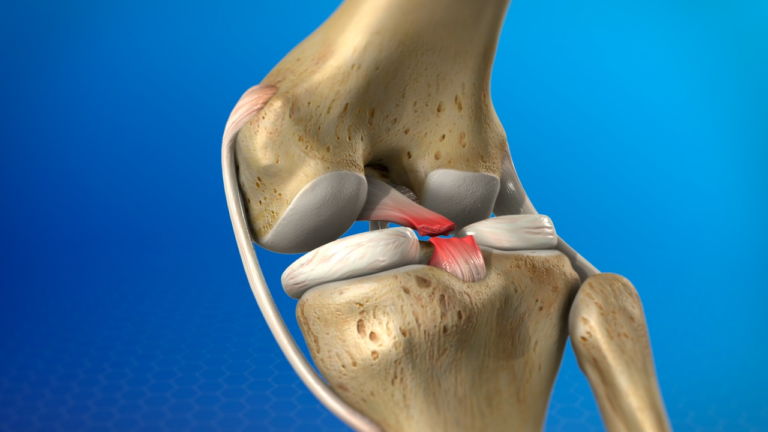

An ACL (anterior cruciate ligament) injury is a common and potentially serious knee injury, especially among athletes and physically active individuals. It…